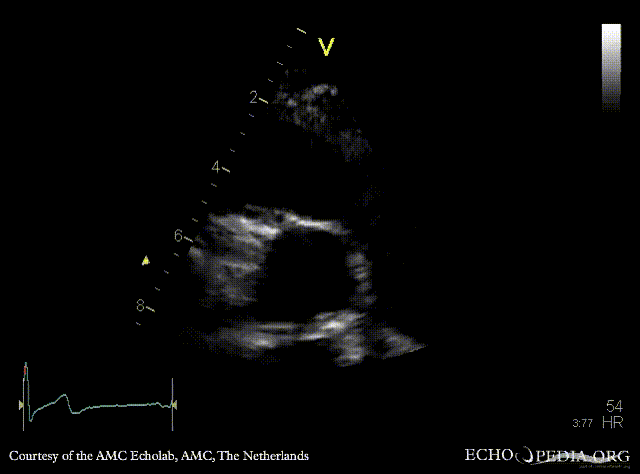

PSAX: Eustachian valve in right atrium, left coronary artery a vue PSAX: right coronary artery a vue